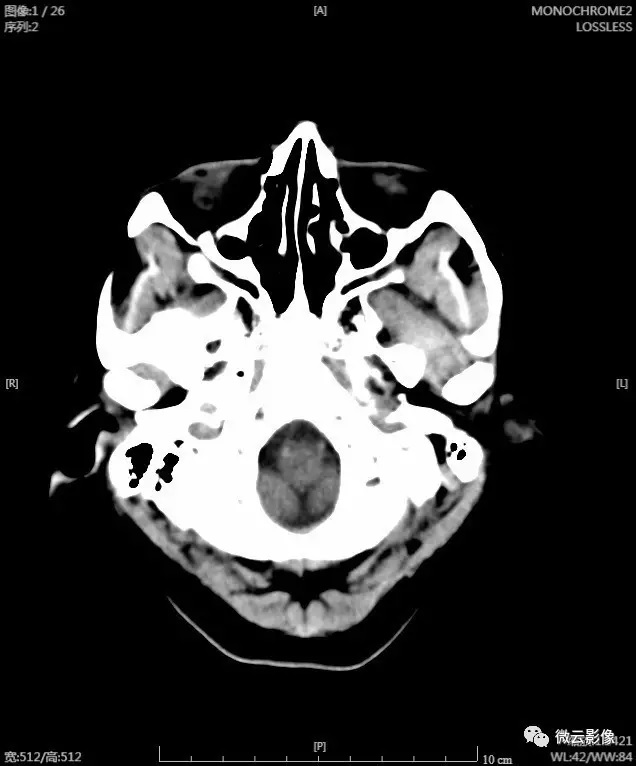

还是老规矩,有图、有数字才有真相,还是让我们用户实际的数字来说话吧。我们使用一组CT的头部扫描图像做测试,图像的大小是现在常见的512*512大小的分辨率,原始未压缩的DICOM文件大小大概在520K左右。

在新版本的压缩算法下,无损影像文件的加载的日志是这样的(见下图)。请重点看图中标红的区域,可以看到单张CT图像的文件大小在100-140K之间,甚至有部分图像是小于100K的。而在我们旧版的图像无损压缩算法下,单张CT图像的大小在200-300K之间。这也就是在上面宣称的相比原来的压缩算法的1-2倍的压缩率的提升,以及相比原始文件的3-5倍的压缩率。